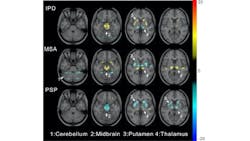

Reston, VA—A new deep learning method has been created to help diagnose parkinsonian diseases, according to research published ahead of print by The Journal of Nuclear Medicine. Using a 3D deep convolutional neural network to extract deep metabolic imaging indices from 18F-FDG PET scans, scientists can effectively differentiate between Parkinson’s disease and other parkinsonian syndromes, such as multiple system atrophy and progressive supranuclear palsy.

To achieve this objective, researchers built a 3D deep convolutional neural network, known as the Parkinsonism Differential Diagnosis Network (PDD-Net), to automatically identify imaging-related indices that could support the differential diagnosis of parkinsonian diseases. This deep learning method was used to examine parkinsonian PET imaging from two groups: more than 2,100 patients from China and 90 patients from Germany.

The deep metabolic imaging indices extracted from PDD-Net provided an early and accurate method for the differential diagnosis of parkinsonian syndromes, with high rates of sensitivity and specificity for Parkinson’s disease, multiple system atrophy, and progressive supranuclear palsy.